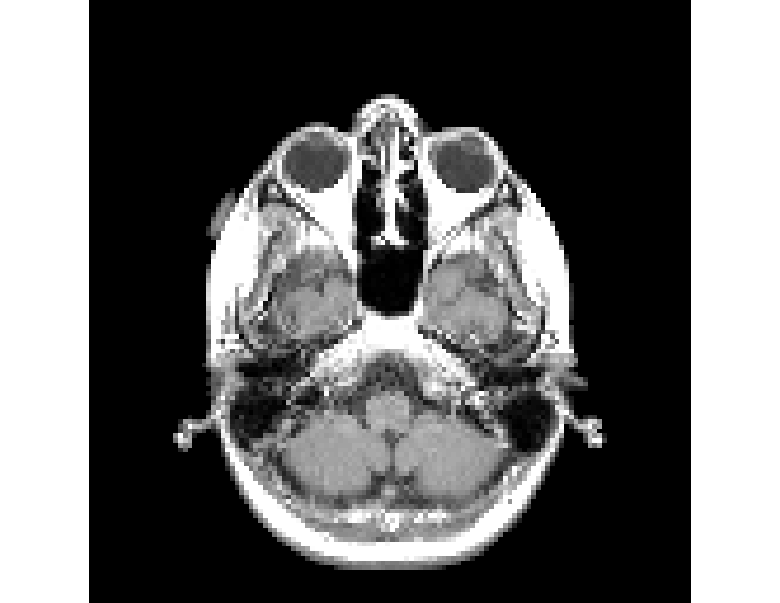

RANDSMAPs are evaluated against three mass-preserving benchmark examples with varying scalability: a moderate-dimensional 1D traffic density dataset from the Lighthill-Whitham-Richards (LWR) hyperbolic PDE; a high-dimensional 2D gray-scale MRI image dataset with sparse observations; and a high-dimensional 2D pedestrian density dataset governed by the Hughes crowd dynamics PDEs. Additionally, two classic low-dimensional manifold learning examples without inherent mass conservation (the classic 33-dimensional Swiss roll and S-curve projected in 2020 dimensions) are included to establish a baseline for RFNN decoder performance. In all examples, RANDSMAPs are compared against the DDM and kk-NN decoders. To ensure fair assessment, all decoders operate on the same low-dimensional embedding/encoding, obtained here via the DM algorithm, though each decoder is, in principle, compatible with any embedding.

Here, we evaluate the performance of the RANDSMAP decoder for pre-image reconstruction, comparing it with the standard RFNN decoder and the numerical analysis-based DDM and kk-NN decoders. The assessment focuses on three mass-preserving physical systems of increasing dimensionality and complexity (Sections 5.1-5.3). To establish a performance baseline in a general non-conservative setting, we also include two classic manifold learning examples, the Swiss roll and the S-curve projected in 2020-dimensions; results for these examples are provided in Appendices E and F.

For both the RANDSMAP (conservative) and RFNN (non-conservative) decoders, we examine three variants distinguished by their random feature mapping: random Fourier features (RFF), multi‑scale random Fourier features (MS‑RFF), and sigmoidal features (Sig). All decoders reconstruct ambient space states from low‑dimensional embeddings obtained via the DM algorithm.

For each problem, the performance of each decoder is evaluated based on (i) reconstruction accuracy, (ii) computational cost, and (iii) conservation accuracy. We quantify the reconstruction accuracy of each decoder by its relative L2L_{2} and LL_{\infty} reconstruction error across the training and testing sets, 𝒳tr\mathcal{X}_{tr} and 𝒳ts\mathcal{X}_{ts}, respectively. To assess computational cost, we recorded the computational times required for both training and inference. Training time includes encoder training (DM algorithm), hyperparameter tuning (of a single parameter for each decoder) over a held-out validation set 𝒳vl\mathcal{X}_{vl}, and decoder training. Inference time covers the complete end-to-end pipeline on the testing set 𝒳ts\mathcal{X}_{ts}, including the encoding to obtain the embedding and the decoding to reconstruct the entire testing set. To assess conservation accuracy, we quantify the pointwise deviation from the exact sum-to-one invariant in Eq. (6). As the RANDSMAP decoder is designed to preserve the sum-to-one invariant by construction, we verify this numerically and demonstrate that it maintains competitive reconstruction performance. To account for the stochasticity inherent to the random feature construction, all reported results for the RANDSMAP and RFNN decoders are averaged over 100 independent runs. The complete implementation details, including dataset generation, train/validation/test splits, feature construction sampling procedures, hyperparameter grids, and solver specifications, are provided in Appendix D.